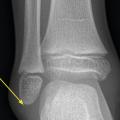

Certaines fractures non ou peu déplacées peuvent être de diagnostic difficile. La fracture de Tillaux touche préférentiellement les adolescentes en fin de croissance, avec une atteinte de l’extrémité distale et latérale de l’épiphyse tibiale. Le tableau clinique mime une entorse de cheville et le trait de fracture n’est pas toujours évident à la radiographie (fig. 3). La fracture étant articulaire, le scanner est souvent nécessaire pour décider d’une ostéosynthèse. Il faut également se méfier des fractures de la base du cinquième méta­tarsien, à ne pas confondre avec le noyau d’ossification secondaire. L’examen clinique permet donc d’orienter le diag­nostic, car la radiographie peut être trompeuse (fig. 4).